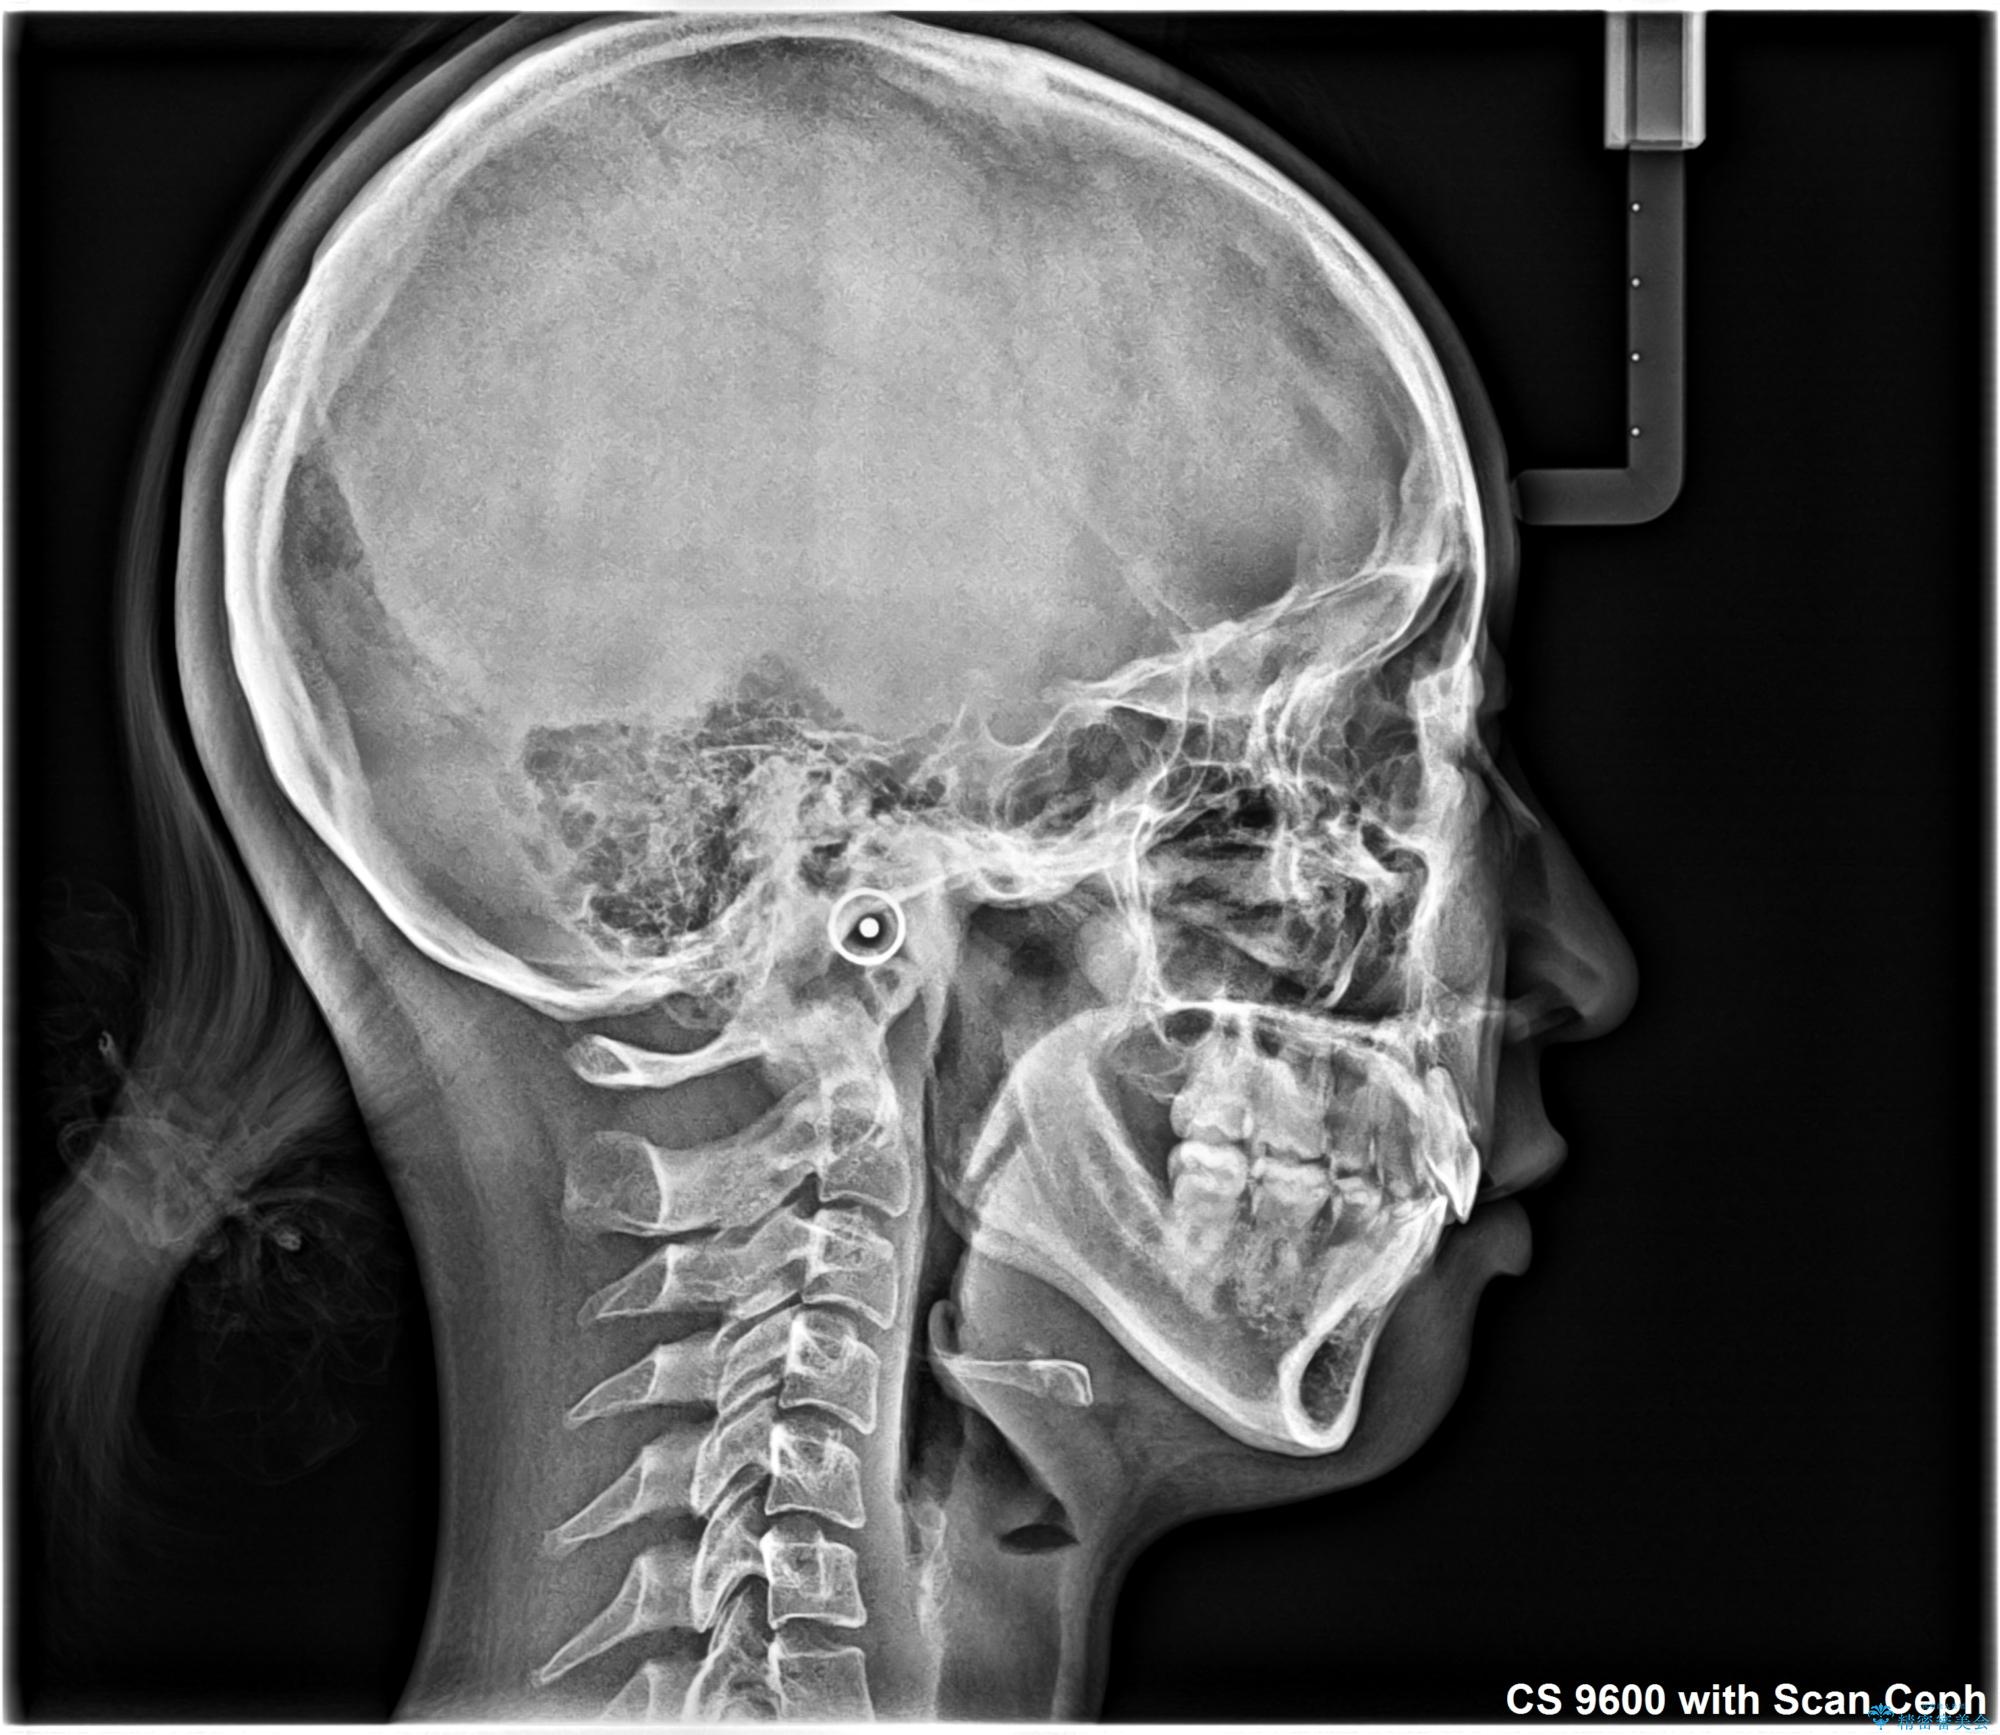

- 上顎前歯が飛び出していて唇がうまく閉じられないとのことで来院された患者様です。

くちばしのように前歯が突出していたため、口元を積極的に引っ込めるために、上下左右の小臼歯4本を抜歯することとしました。

また、上顎歯列が下顎に対して前方位に位置していたため、補助装置を用いて上顎歯列を後方に移動させ、より積極的に口元を下げるようにしました。